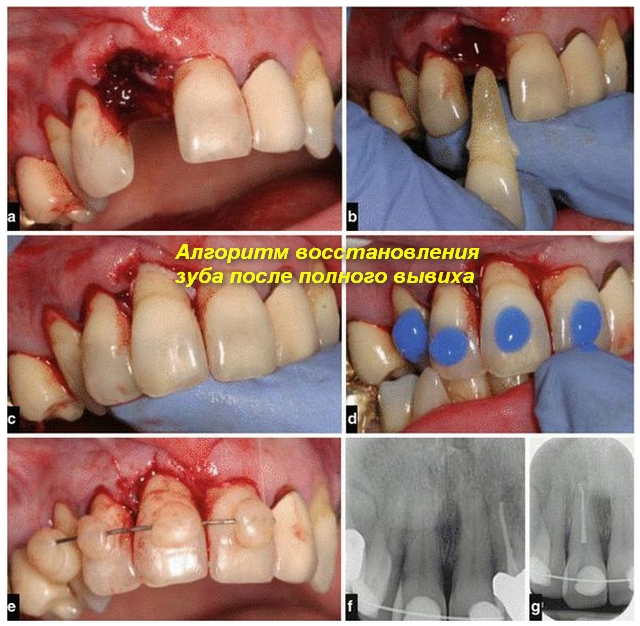

Полного

В данной ситуации терапия включает:

• удаление пульпы и пломбирование каналов;

• реплантацию зуба;

• фиксацию зуба;

• соблюдение щадящей диеты пациентом.

При осмотре лунки специалист оценивает ее целостность. Возможность реплантации при полном вывихе зависит от нескольких факторов:

• тип зуба: молочный или коренной;

• степень тяжести травмы;

• состояние корня: завершено ли его формирование.

Реплантация может быть:

• одномоментной — зуб сразу ставят на место и фиксируют шиной;

• отсроченной — зуб помещают в специальный раствор и хранят в холодильнике несколько дней перед приживлением.

Обратите внимание!

После реплантации пациенту необходимо сделать контрольные рентгеновские снимки через определенные интервалы.

Если зуб успешно занимает свое место в лунке, шину обычно снимают. В противном случае врач назначает повторное лечение или удаление поврежденного зуба.